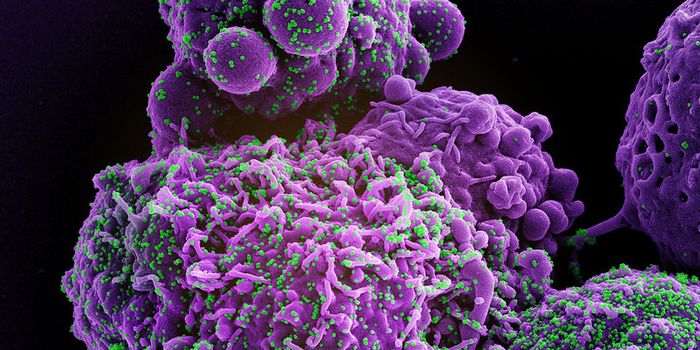

MAY 23, 2024MicrobiologyWhen human immunodeficiency virus (HIV) emerged and was identified as the cause of acquired immunodeficiency syndrome (A ...